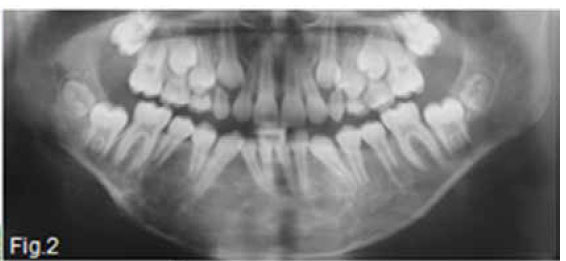

Figure 1 & 2 shows an aggressive lesion in a 14 year old male patient. The pantomograph show the lesion extending from the 36 to the 46. Expansion of the cortex and divergence of the roots is discernible. A histological diagnosis of a Central giant cell granuloma (CGCG) of the bone was made. The original term of CGCG was coined by Jaffe in 1953, when he suggested that this lesion should be distinguished from the Central giant cell tumour (GCT) of bone. Jaffe believed that the CGCG is a reactive lesion, whereas the CGT is a neoplasm. Central giant cell granuloma of the jaws is considered to be a fairly common benign reactive lesion. It is characterized by the presence of numerous multinucleated giant cells. The CGCG most commonly affects young people and over 50% of cases occur in the first two decades of life. The average age of occurrence is 21 years, with a range of 3 to 68 years. Females are affected slightly more than males. The mandible is affected in the majority of cases, with the anterior segments being affected more often than the posterior. Radiographically the lesion is essentially radiolucent, often with a multilocular, soap bubble appearance (Fig.3). A rather marked expansion with thinning of the cortical plates is a characteristic finding (Fig.4). The tumour usually destroys the lamina dura and causes displacement of the teeth (Figs.2 & 3). It may lie in intimate contact with the teeth, causing very few changes; in other areas it may cause extensive root resorption. This root resorption is usually irregular and leaves a ragged surface in contrast to the smooth resorption seen in association with cysts. According to Langlais et al.(1994), CGCG's can present with an aggressive or non-aggressive behaviour. The basis for this division consisted of histologic, clinical and radiological factors. The radiological features of the aggressive type include resorption of adjacent root apices, perforation of the expanded cortex and a diameter exceeding 2cm; nonaggressive lesions are characterized by the absence of root resorption, intact cortices and a diameter smaller than 2cm. A peripheral variant of this lesion occurs in the gingiva and produces an epulis-like soft tissue mass in the gingival region. In a edentulous area it may result in a nodule or swelling on the alveolar ridge and may present radiologically with a typical "peripheral cuffing" (red arrows, Fig.5). The CGCG are known to recur, and recurrence is a feature of the aggressive type and may require curettage plus peripheral ostectomy A histological diagnosis of CGCG must always be followed by a workup for the possibility of the presence of a "Brown" tumour of hyperparathyroidism.